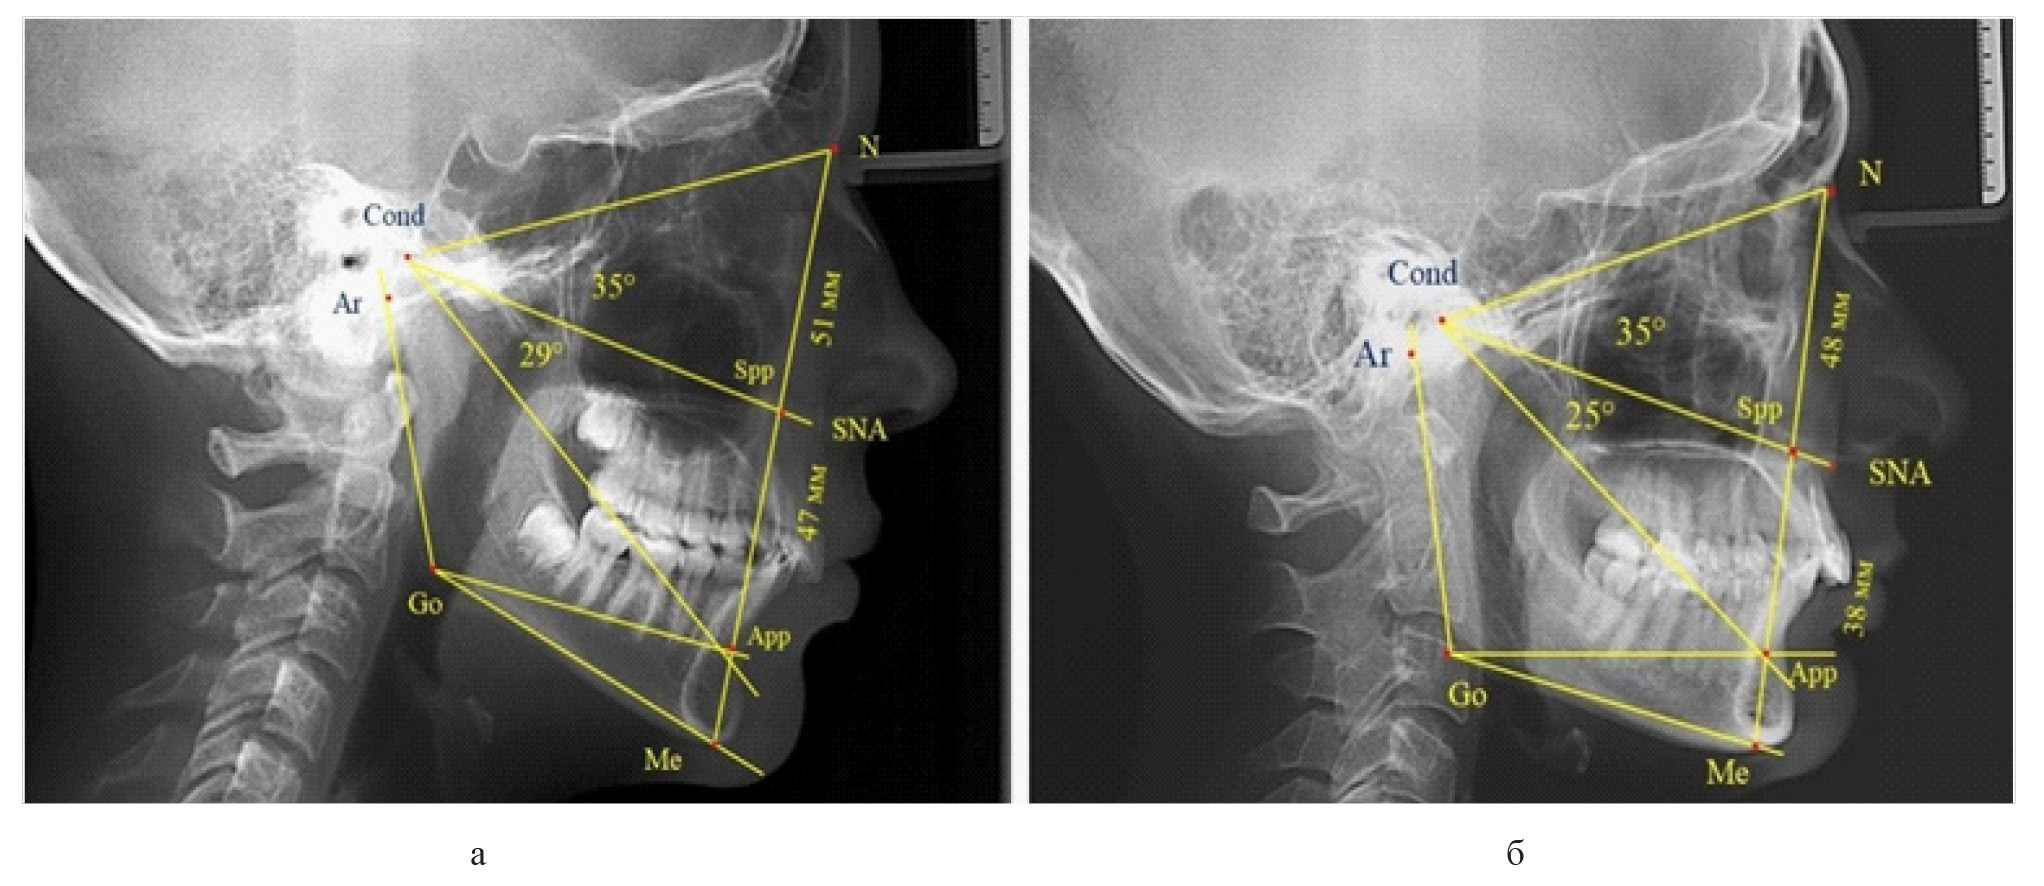

Вертикальная линия передней высоты лица (N-Me), после ее пересечения с линией Cond-SNA, определяла положение точки Spp, при этом вертикаль N-Spp использовалась в качестве оценки высоты назального отдела лица. Продолжение линии Go-Api до пересечения с линией N-Me позволяла определить положение конструктивной точки Арр и оценить линейные размеры гнатической части лица по величине вертикали Spp-Арр (рис. 1).

Рис. 1. Методы оценки основных параметров ТРГ для определения вертикальных размеров лицевого отдела головы

Величина угла назального отдела лица (N-Cond-SNA) в исследуемой группе составила (35,28 ± 0,26)°, а линейные размеры (N-Spp) были (48,82 ± 0,96) мм. Параметры угла гнатической части (SNA-Cond-App) были (29,83 ± 0,54)°, при линейной высоте (49,25 ± 1,31) мм.